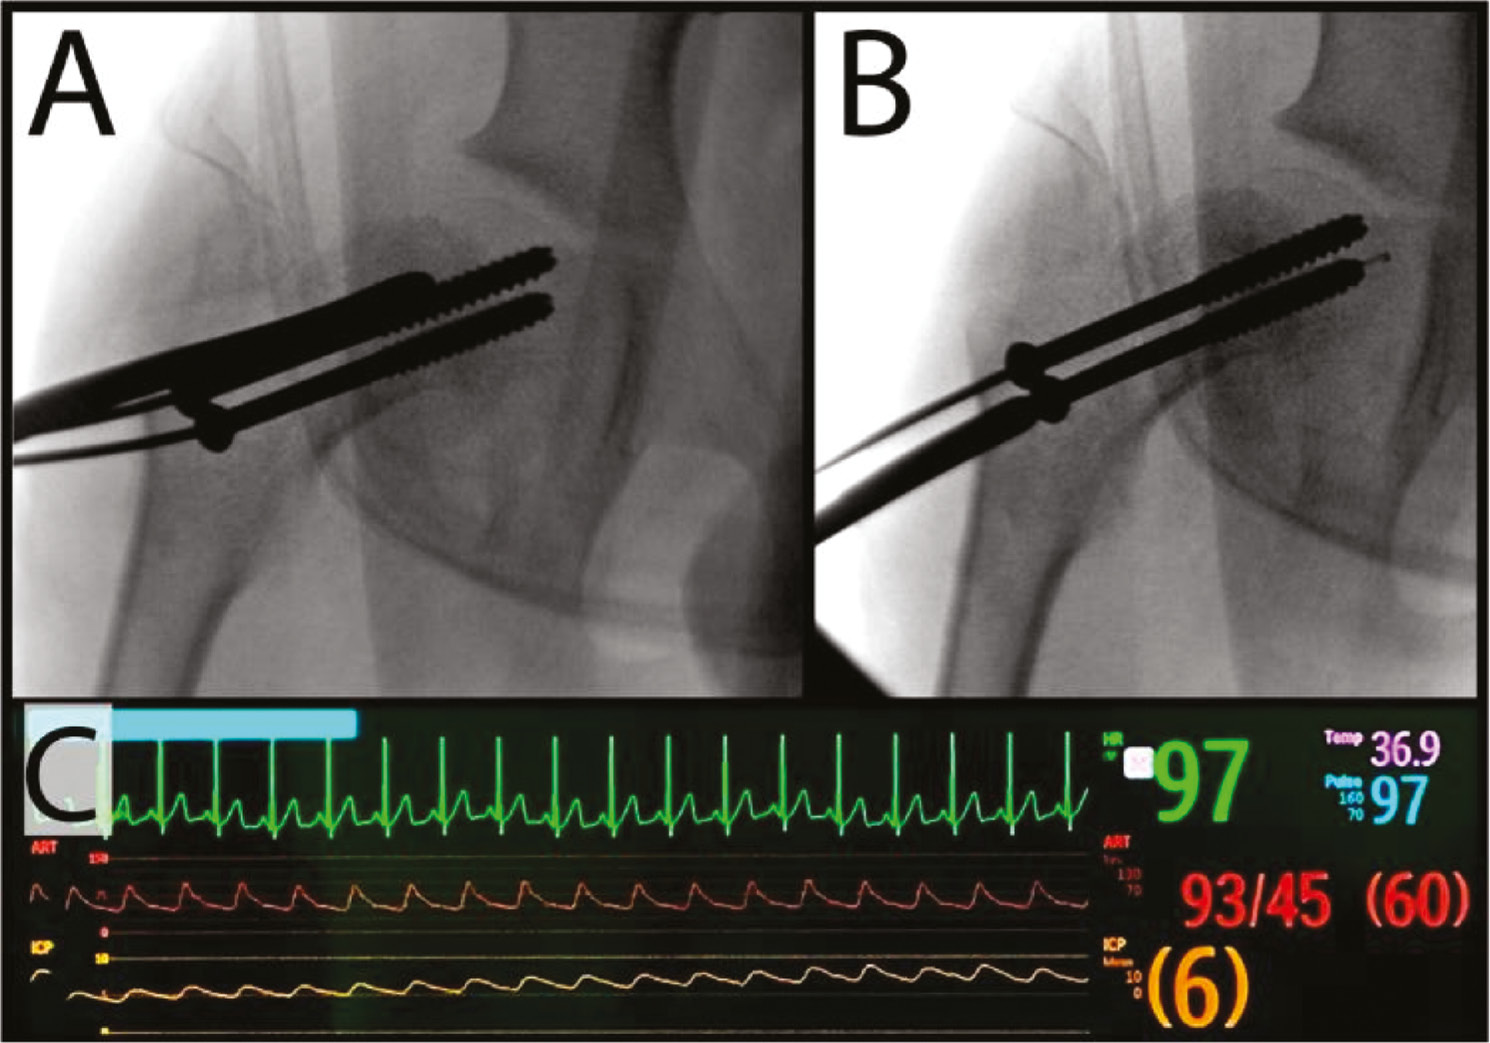

In an attempt to further reduce rates of osteonecrosis associated with unstable SCFE, Schrader et al.57 described a technique for intraoperative monitoring of epiphyseal perfusion. An intracranial pressure (ICP) probe was inserted percutaneously through a cannulated screw into the epiphysis. The presence of a pulsatile waveform synchronous with cardiac monitoring suggests that perfusion to the epiphysis is maintained. This technique provides not only prognostic value but may also help confirm the adequacy of the capsulotomy performed after fixation of an unstable SCFE (Figure 5).

Figure 5. In cases of unstable SCFE, a capsulotomy is performed (such as with a Cobb elevator) to decompress intracapsular hematoma, which could otherwise lead to tamponade and decreased epiphyseal perfusion. (A) An intracranial pressure sensor can be threaded through the cannulated screw in the epiphysis. (B) Sensor seen extending beyond the tip of the inferior screw to assess for femoral head perfusion. A pressure waveform (C, orange) from the intracranial pressure sensor that is synchronous with the cardiac monitoring (C, green waveform) is prognostic of maintained epiphyseal perfusion.